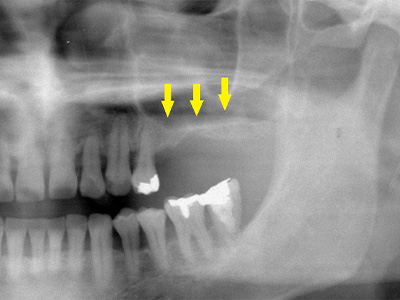

40代女性。上顎前歯を抜歯、虫歯と歯槽膿漏の状態が悪く、抜歯されたのですが、歯を支える歯槽骨が大きく吸収されてしまっていました(黄色矢印)。

インプラント治療を希望されていたのですが、下顎骨の中を通る神経(赤色矢印)が近接していて、骨が不足しているためインプラントの埋入が困難な状況でした。 -